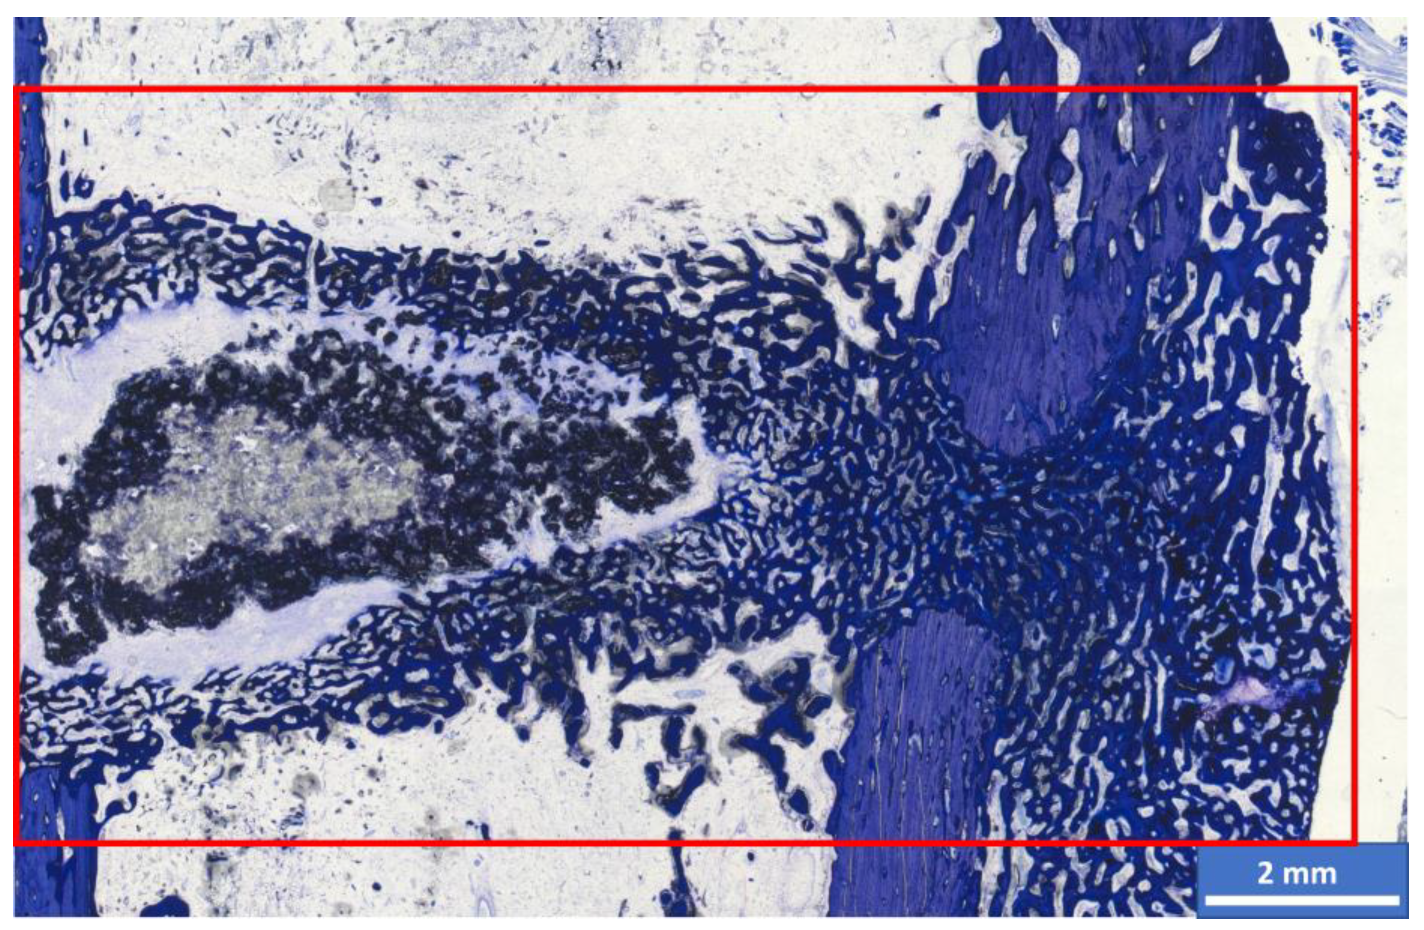

2.5. Histological Examination and Semi-Quantitative Evaluation

Histomorphometric Examination

3.6. Histological Examination

3.6.1. Semi-Quantitative Assessment

3.6.2. Histomorphometric Examinations